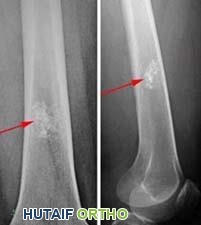

تُوفر الأشعة السينية صورًا للهياكل الكثيفة مثل العظام. في الأشعة السينية، تظهر الأورام الغضروفية الداخلية عادةً على شكل أورام صغيرة (أقل من 5 سم)، ذات شكل فصي، ومناطق داكنة في منتصف العظم. غالبًا ما تحتوي على بقع بيضاء أو تكلسات داخلها. تُشير المناطق البيضاء في الورم إلى نمط من الحلقات والأقواس، مما يدل على أن الورم يحتوي على غضروف.

الأشعة السينية، مأخوذة من الأمام (يسار) والجانب (يمين) تُظهر ورمًا غضروفيًا داخليًا حميدًا. تم اكتشاف الورم عند إجراء الأشعة السينية بعد إصابة في الركبة.